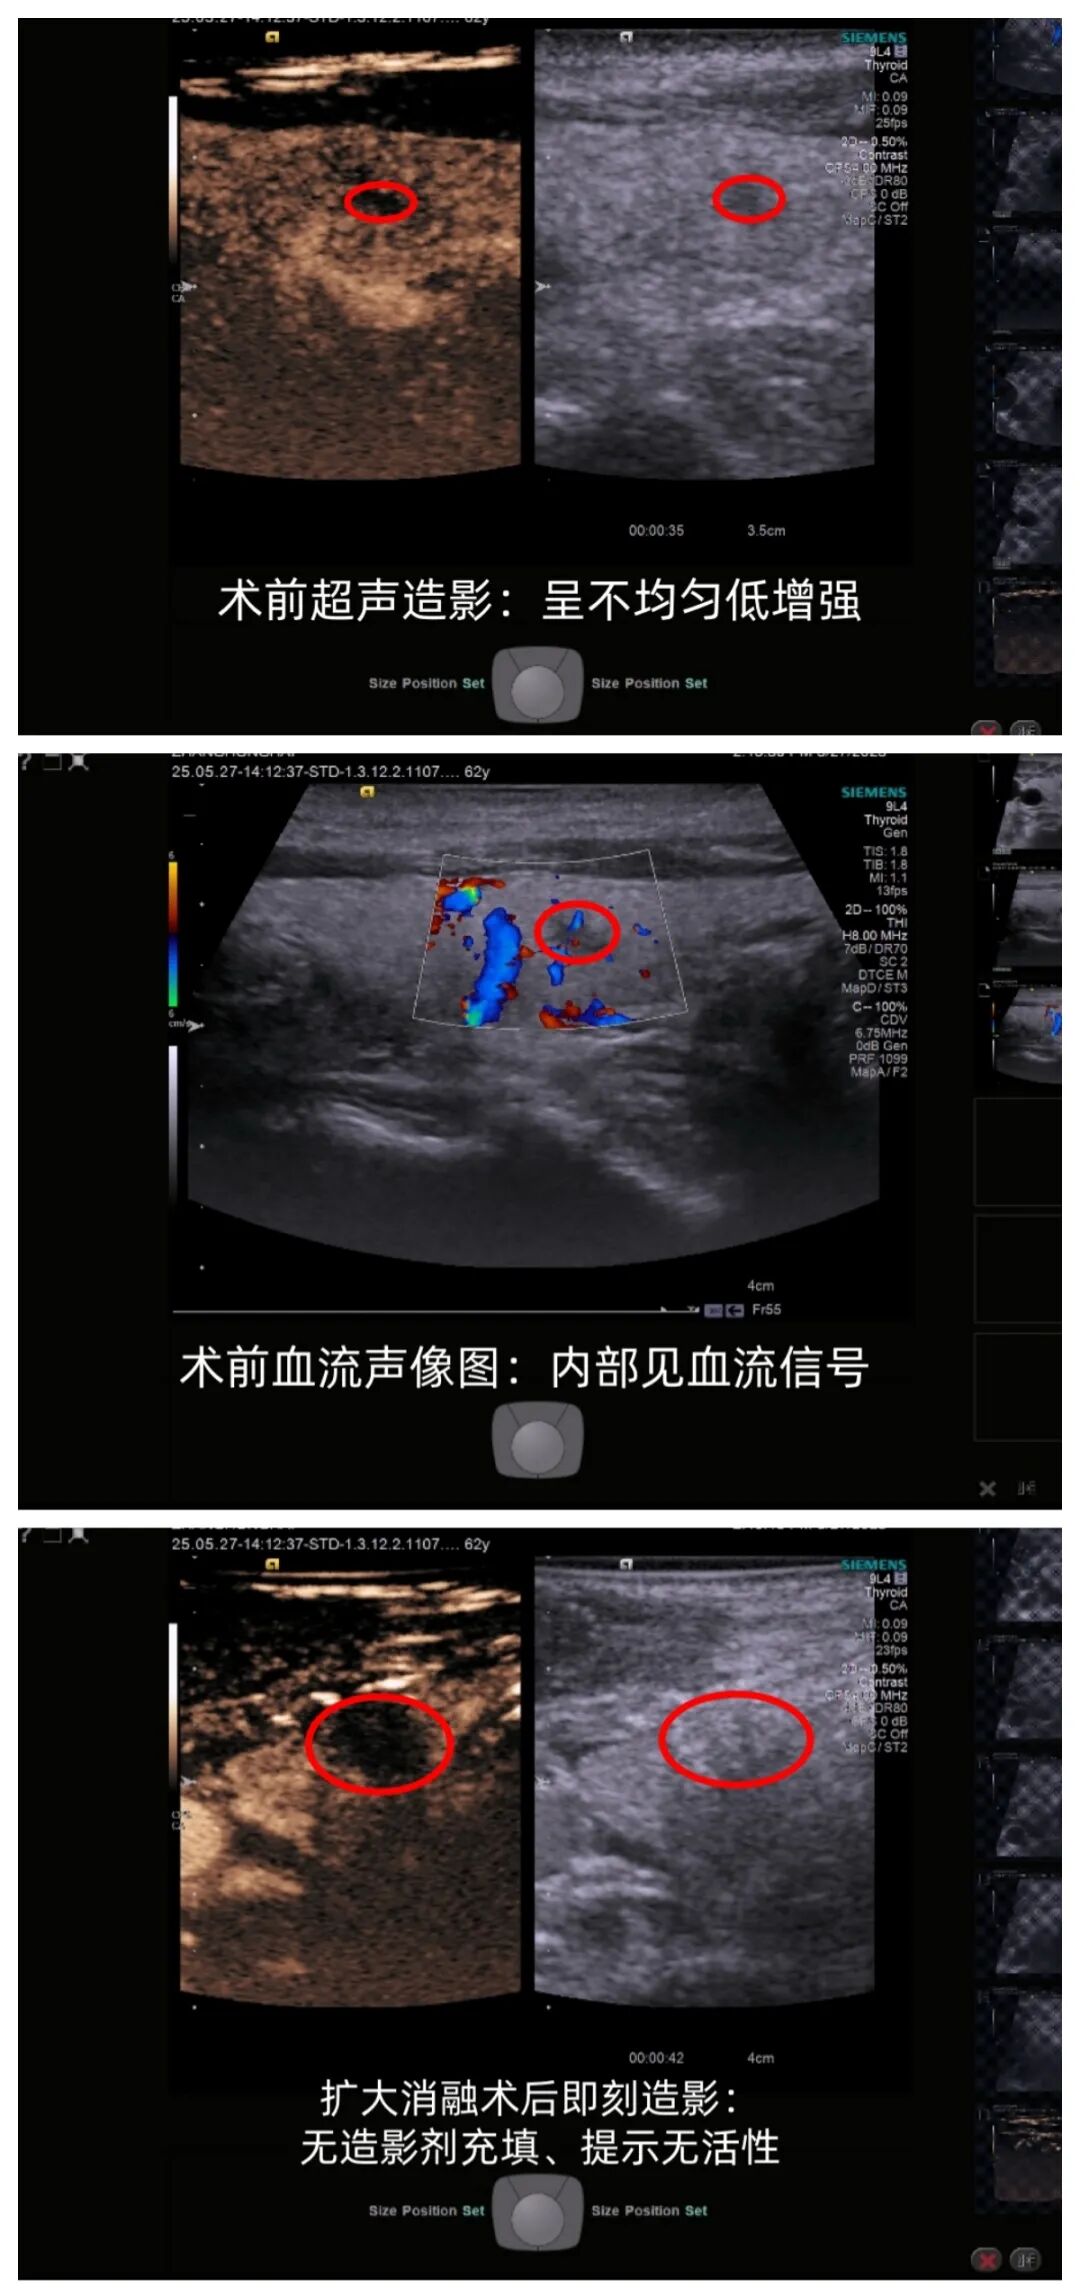

近日,62岁的张先生发现甲状腺有一肿物,穿刺后病理显示为“甲状腺乳头状癌”。考虑患者具体情况,我院超声科主任、主任医师娄可新为他实施了“彩超引导下肿瘤微波消融术”。在超声的引导下,消融针精准避开血管神经,穿刺至癌灶中心,像导弹一样精准摧毁目标。术后,5分钟行超声造影确认癌灶坏死,且凝固形成的“反应带”进一步阻断肿瘤供血,降低转移风险,张先生很快恢复出院了。